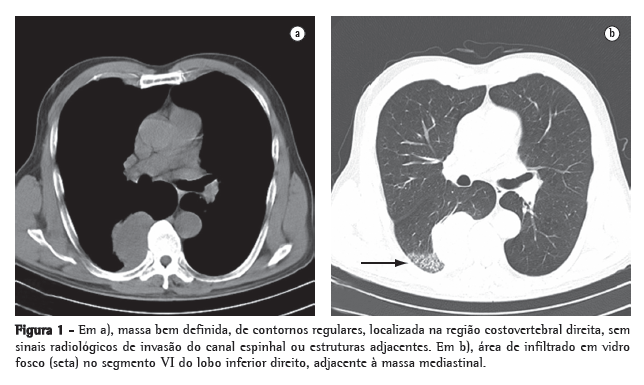

Ao exame físico apresentava-se em bom estado geral e nutricional, e seus sinais vitais eram normais. Sem adenomegalias. A ausculta pulmonar mostrava estertores finos inspiratórios em ambas as bases pulmonares. A ausculta cardíaca era normal. O exame do abdome e dos membros inferiores não revelou alterações. Os resultados do hemograma e testes bioquímicos estavam dentro dos padrões de normalidade. A tomografia computadorizada do tórax (Figura 1a) revelou massa bem definida, de contornos regulares, localizada na região costovertebral direita, medindo 6 × 4,3 cm. Adjacente a massa, observava-se infiltrado pulmonar, aparentemente inflamatório e não-específico.

(Figura 1b)